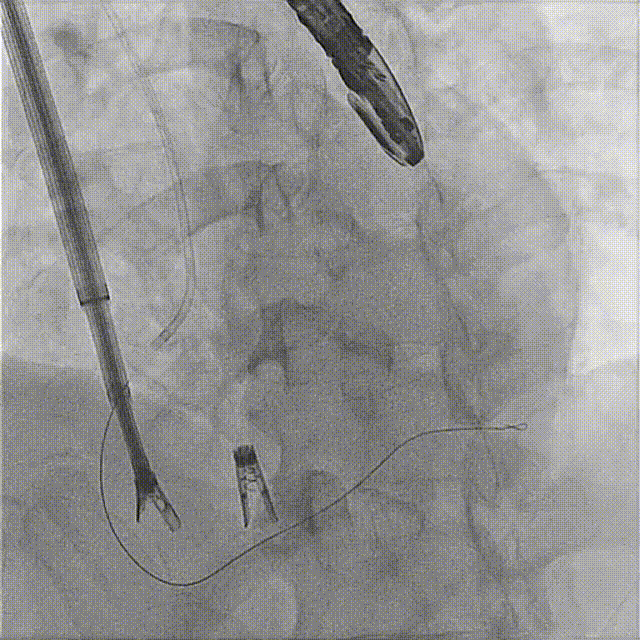

7. Coronary artery course and blood supply were evaluated under DSA (the course of the coronary artery was altered, but blood supply remained normal).

The first clip was initially implanted at the posterior‑septal commissure, which resulted in deformation of the coronary artery course. The first clip was released and repositioned toward the septal leaflet, with the clip arms opened to cross the posterior‑septal commissure before re‑implantation.

Initial DSA after clipping indicated compromised blood supply. The clip was therefore released, repositioned, and redeployed.

The second clip was deployed toward the septal leaflet, crossing the posterior‑septal commissure and positioned flush with the tricuspid annulus.

During implantation of the second clip, anchoring was performed at the annulus near the leaflet base. Intraoperative DSA showed no impact on the coronary arteries, and good right coronary perfusion was confirmed after deployment.